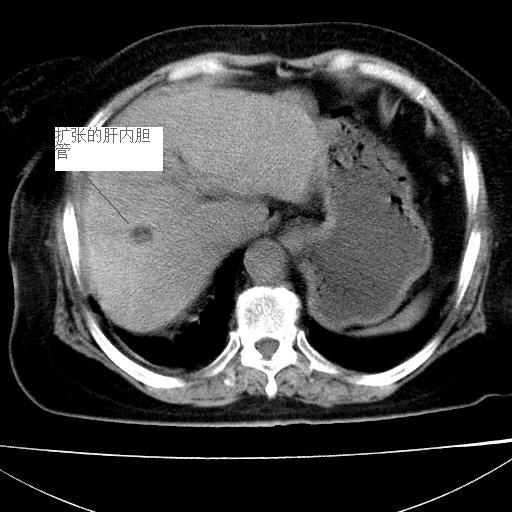

患者女74岁;右上腹胀痛1月,伴恶心,无发热;生活在疫水区。有术后病理及术后半年的追踪ct.

1)慢性血吸虫病(典型)。2)肝硬化。3)肝癌?4)胆囊炎。5)少量腹水。6)右侧少量胸腔积液。

支持.边缘见高密度线条样钙化影.

肝脏体积缩小,肝裂增宽,边缘不平呈波浪状,肝右叶见分隔状条索形钙化,亦见多结节低密度灶,边界不清,肝周可见少许液性暗区,胆囊增大内密度均匀,脾脏下缘低于脏脏的下缘,胸腔亦见液性暗区,余未见明显异常.

诊断:1肝硬化并慢性吸血虫病,脾肿大

2肝内占位,考虑肝癌可能性大,建议做增强

3胆囊炎, 4少量腹水及胸水

胆囊增大饱满,壁增厚。胆囊颈部见软组织密度影。临近肝右叶前段见片状低密度区,病灶下部见条状钙化,少量胸腹腔积液。意见:胆囊颈癌累及肝脏。

病人以胆囊癌手术的,病理结果为中分化腺癌。

现在看看肝右叶内圆形低密度影你们考虑什么呢?

肝内圆形低密度影考虑扩张的胆管

请看3mm重建像如下: